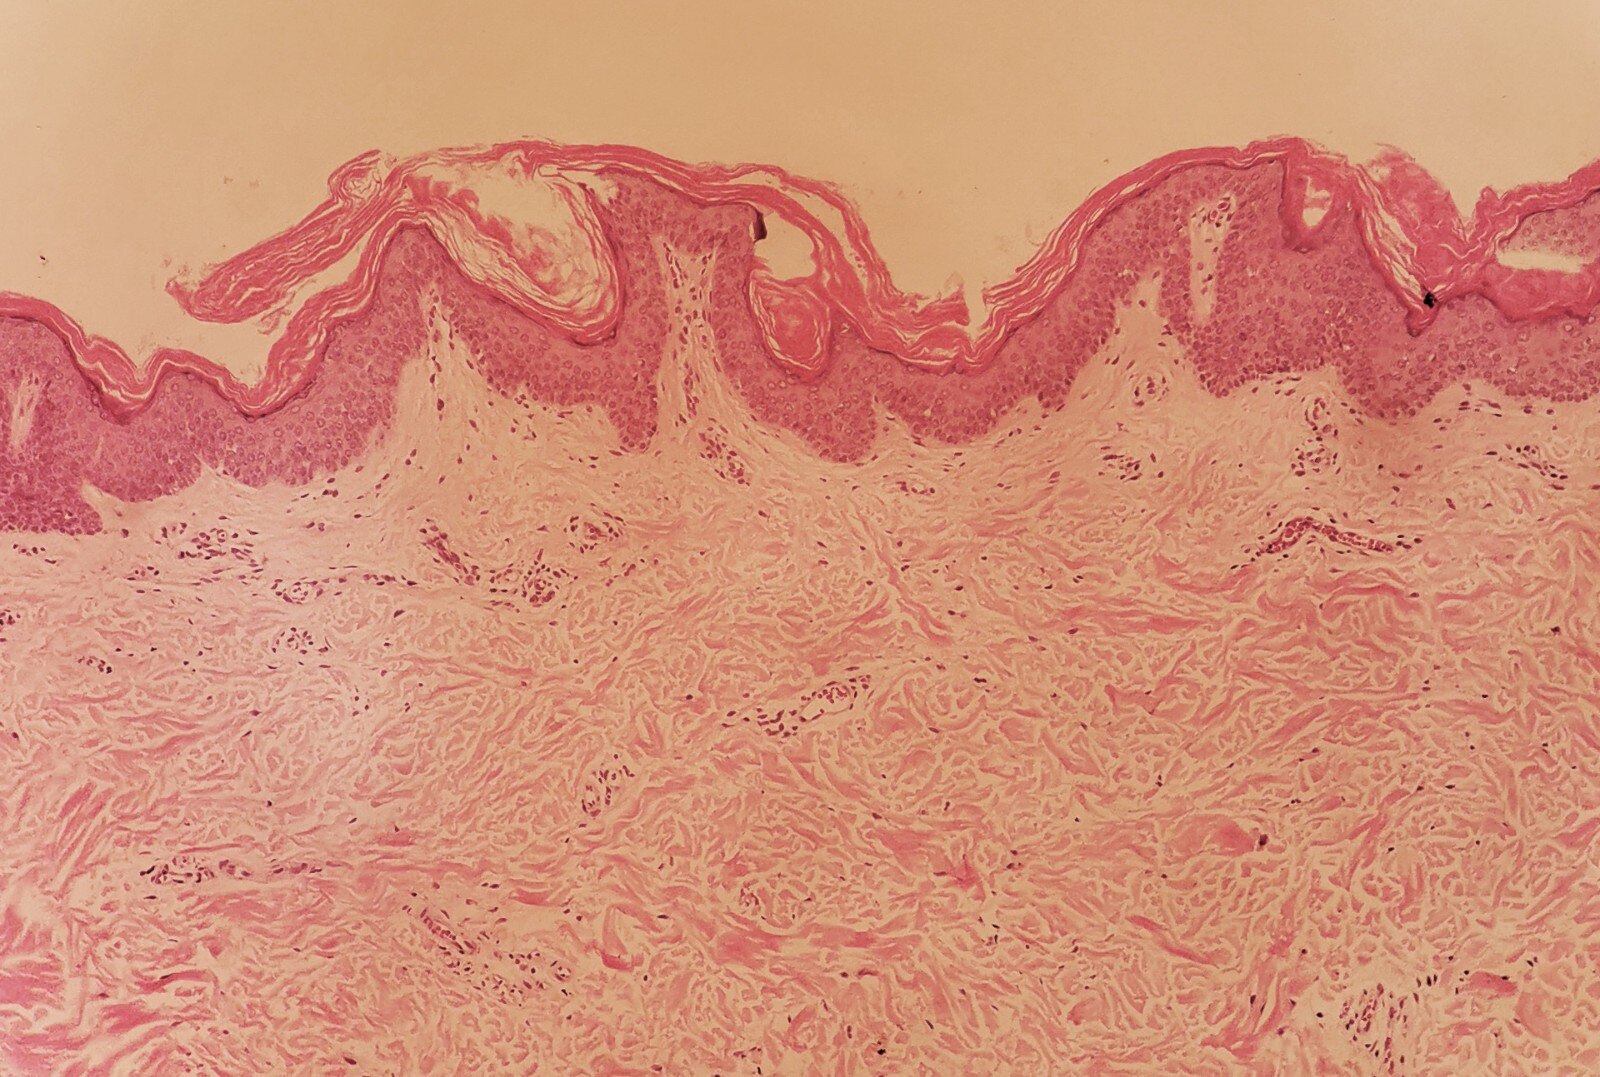

表皮网篮状角化过度及轻度乳头瘤样增生,真皮浅层血管周围散在单一核细胞浸润。

CRP 皮损发展缓慢,通常呈慢性病程。皮损一般开始于胸、腹、背部,以躯干为中心,并可逐渐向两侧蔓延,皮损中部可融合成片,周围呈网状分布,也有皮损呈波纹状分布的报道,主要好发部位为躯干上部、腋下和颈部。但也可见于肘窝、腘窝、耻骨上区等少见部位。CRP 一般为散发病例,但可见家族性发病的报道,这提示CRP可能和遗传相关。 CRP 的皮损组织病理表现为角化过度,乳头瘤样增生,乳头间表皮呈不同程度的棘层肥厚,可见基底层色素增加,真皮浅层血管轻度扩张,管周少许单一核细胞浸润,可见噬黑素细胞。临床上,本病主要与花斑癣、黑棘皮病、疣状表皮发育不良等疾病相鉴别。